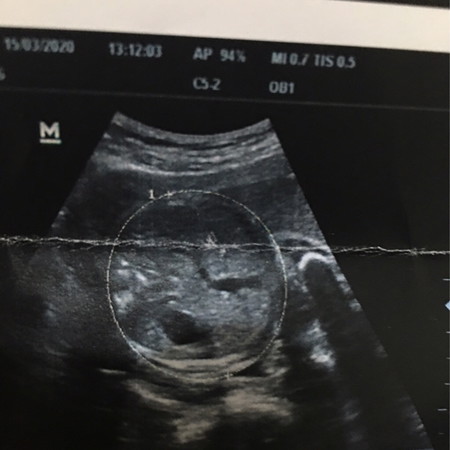

สอบถามแม่ๆหน่อยค่ะ ตรงนี้ใช่ใบหน้ากับมือน้องใช่ไหมค่ะ

เป็นช่วงที่คุณหมอวัดศรีษะน้องค่ะแม่

แม่บ้านนี้ดู ก็ว่า ใช่ค่ะ